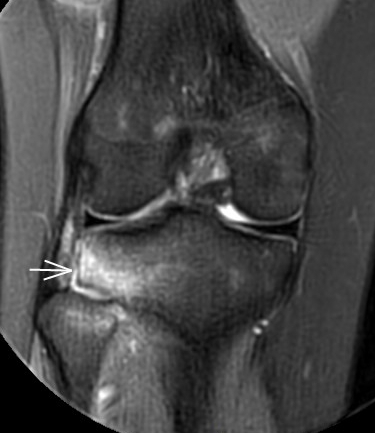

3. 上下樓“針刺痛”——軟骨的“磨砂紙預(yù)警”

場(chǎng)景:爬樓梯時(shí)膝蓋刺痛,久坐后僵硬如“生銹齒輪”

MRI偵查:發(fā)現(xiàn)軟骨變薄、缺損(早期骨關(guān)節(jié)炎信號(hào)),趕在“路面塌方”前修復(fù)

(軟骨損傷)